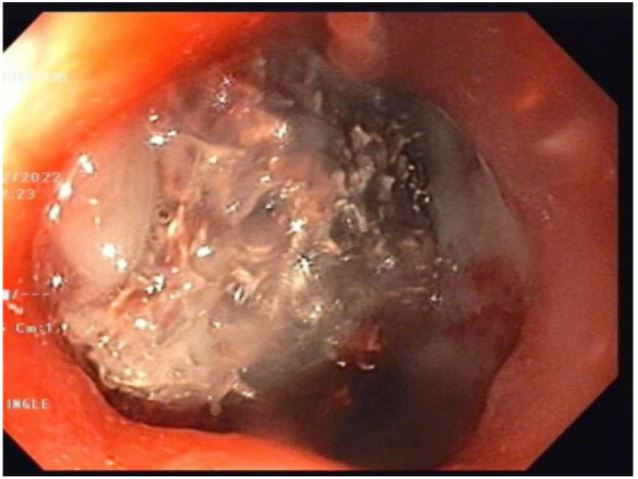

Case capsule 3

A 65 year lady a case of squamous cell carcinoma of lower end of oesophagus, she has received neoadjuvant chemoradiotherapy and underwent total esophagectomy and gastric pull up, 2 weeks later she presented with fever and shortness of breath after routine work up CECT chest and upper abdomen was done s/o 7mm defect in posterior wall of pulled up stomach at the level of D 6 vertebra with the leak of oral contrast forming a 6.5 x 2.2 x 1.2 cm collection in right paravertebral region from D5 to D8 vertebral level. She was treated with IV antibiotics and other supportive measures. Upper GI endoscopy showed a large fistulous opening with an overlying slough in the posterior wall of the pulled-up stomach along the staple line (Figure 7). She continued to have a fever, so CT-guided pigtailing was done, and pus was sent for Culture sensitivity, and antibiotics were changed according to it. One week after the procedure, a repeat CECT chest and upper abdomen was done. The previously seen right posteromedial collection showed a decrease in size, but a contrast leak persists. She was continued with antibiotics and supportive measures. Her fever subsided, but for persistent fistulous openings, therapeutic options were excision of the stomach, esophagotomy, and covered stents. For the present case, we went ahead with indigenously modified E-Vac therapy, which was performed for a total of 26 days while the sponge was changed four times. During the first three changes, the sponge was placed directly into the cavity. Excellent granulation of the tissues around the leak was achieved, together with a progressive reduction of the cavity size and of the pleuro-mediastinal abscess (Figure 8). Daily output from the collection bag dropped After 6 weeks of initiation of the E-vac therapy, the cavity showed complete healing, a CT scan showed a small pseudodiverticulum but no leak, and she was started on a full oral diet.

Figure 8: Endoscopic image Anastamotic site leak with overlying slough in cavity after gastric pullup.